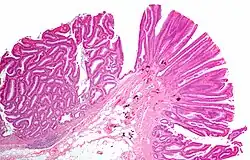

Villous adenoma

Micrograph of a colorectal villous adenoma. H&E stain

These adenomas may become malignant (cancerous). Villous adenomas have been demonstrated to contain malignant portions in about 15–25% of cases, approaching 40% in those over 4 cm in diameter.[7] Colonic resection may be required for large lesions. These can also lead to secretory diarrhea with large volume liquid stools with few formed elements. They are commonly described as secreting large amounts of mucus, resulting in hypokalaemia in patients. On endoscopy, a "cauliflower' like mass is described due to villi stretching. Being an adenoma, the mass is covered in columnar epithelial cells.